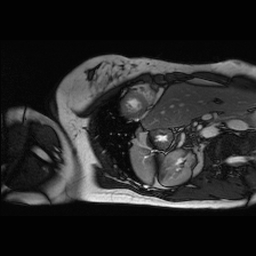

Figure 3 presents a qualitative comparison of segmentation performance on examples from the Synapse, BTCV, ACDC, and ISIC17 datasets. The first two examples (from Synapse) highlight variations in segmentation performance among U-Net, TransUnet, Mamba-Unet, and Swin-Unet. While Swin-Unet performs well in the first example, its performance decreases in the second example, particularly in segmenting the organ highlighted in blue. Additionally, it misclassifies background regions as the class highlighted in orange. In contrast, our approach demonstrates high robustness in segmenting all classes accurately and aligning well with the ground truth masks.

Across BTCV, ACDC, and ISIC17, the comparison methods exhibit varying performance depending on the task and class. For instance, Mamba-Unet struggles to segment multiple organs in BTCV, even misclassifying certain classes as others. In the ACDC dataset, both TransUnet and Mamba-Unet perform poorly in segmenting the three classes. In the last column (ISIC17), Swin-Unet oversegments the skin lesion compared to the ground truth. Unlike the comparison models, our approach consistently delivers effective segmentation across different tasks and datasets.

These qualitative findings further reinforce the quantitative results presented in the experimental section, demonstrating the effectiveness of our MambaCAFU model in handling binary and multi-class segmentation across diverse medical imaging modalities and tasks.

Slice GT Unet TransUnet Mamba-Unet Swin-UMamba MambaCAFU-V1

Figure 3: Visual comparison of segmentation examples from Synapse (first two examples), BTCV (3-4 examples), ACDC (5th example) and ISIC17 (last example). Columns: input slice, ground truth, Unet, TransUnet, Mamba-Unet, Swin-UMamba, and MambaCAFU-V1.